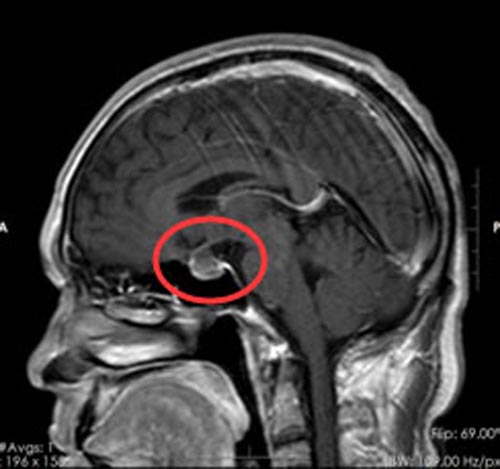

急诊行脑部MRI检查,鲁明副院长仔细阅片后,发现在头颅垂体的位置出现高信号,垂体前后叶间类圆形占位病变,大小约1.6cm×1.3cm×1.2cm,垂体柄受压前移,根据患者的一系表现和生化检查考虑是垂体卒中,脑垂体瘤腺瘤出血,压迫了视网膜及海绵窦内的动眼神经,导致动眼神经麻痹,视物重影。

▲手术前